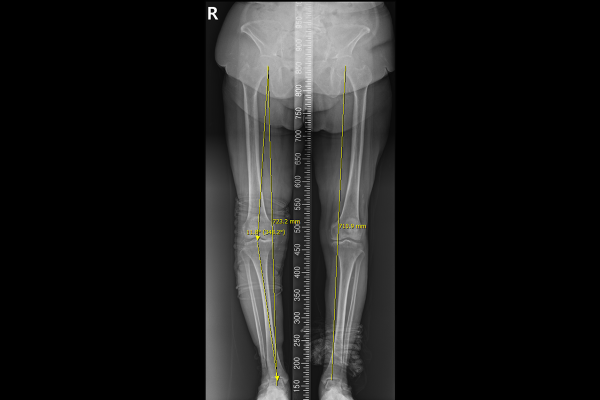

다리 정렬을 확인하기 위해서 반듯하게 서서 촬영하는 검사인 스캐노그램(Scanogram)을 시행했을 때, 다리 정렬이 정상범위인 5도 이내를 넘어선 11도로 O다리 변형되었음을 확인하였습니다.